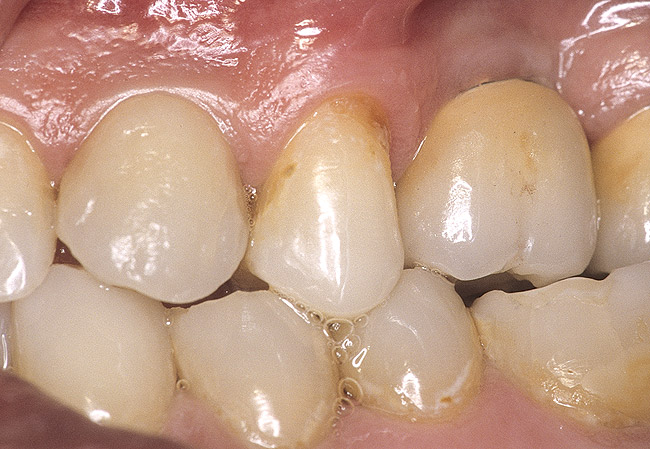

Case 3

A 53-year-old female was referred for evaluation of a fracture of tooth No. 24. The tooth had been treated endodontically 5 years prior. The radiograph revealed a complete fracture of the tooth involving the crown (Figure 12). Tooth extraction and immediate placement of a an implant that was 10 mm in length and 3.75 in diameter was planned.

At the time of surgery, the tooth was extracted without harvesting any mucosal flap because the implant site was prepared by means of a pilot drill bur (Figure 13) and alternating osteotomes (Figure 14A and Figure 14B). The implant was positioned and showed primary stability. The implant was loaded 2 days after surgery. Then, splinted PFM crowns supported by custom gold abutments were delivered. At 6 months posttreatment, the radiograph revealed no bone resorption and the clinical result was optimal (Figure 15A and Figure 15B).

Figure 15 A Final implant-supported PFM restorations.

Figure 15a  Final implant-supported PFM restorations.

Figure 15a